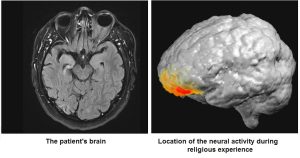

Arzy a Schurr byli proto schopni zkoumat neurální korelace chování. Ukazuje se, že došlo k nárůstu aktivity v pásmu nízkých gamma vln (30-40 Hz) lokalizovaném na levém prefrontálním kortexu (3), ke kterému došlo při nástupu náboženského zážitku.

Autoři dospěli k závěru, že tento člověk trpěl „grandiózní náboženskou iluzí zjevení a misionářské horlivosti v kontextu post-ictal psychózy (PIP)“. PIP je forma psychotické epizody, která se může objevit po epileptických záchvatech. Co se týče postižení prefrontální kůry v tomto zážitku PIP, Arzy a Schurr říkají, že tento region je zapojen do jiných forem psychózy, ale nakonec to zůstává tajemstvím: nevíme, co se stalo, nebo co způsobilo abnormální aktivitu v této konkrétní oblasti oproti ostatním. (Autoři také neříkají, jak řídí artefakty svalů a očí EEG.)